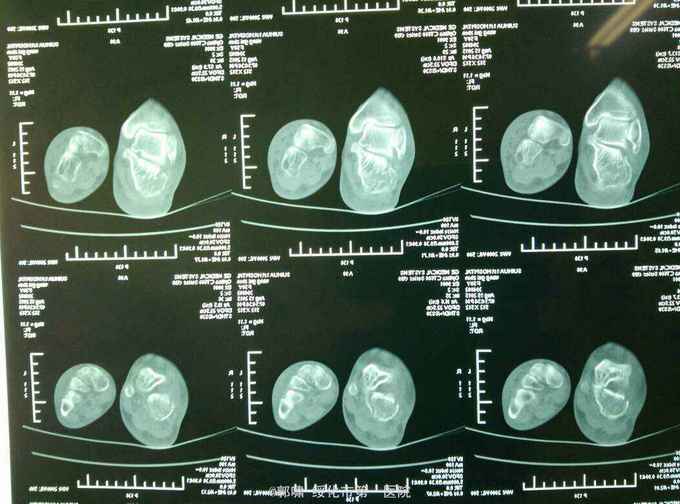

诊断。右跟骨粉碎性骨折。病人入院后常规检查。急诊腰麻下闭合复位。横向挤压恢复跟骨横径。克氏针撬拨恢复跟骨贝雷氏角。恢复跟骨关节面平整。沿跟骨长轴交叉传入细克氏针。拧入空心钉。

跟骨粉碎性骨折。治疗困难。现在治疗方法较多。很多同仁发布了内固定钢板方法。效果很好。但我们基层医院没有类似钢板。急诊应用空心钉。只要掌握技巧。效果也不错。作为补充吧。跟骨骨折必须做到关节面平整。贝雷氏角恢复。跟骨长轴恢复及横径恢复。然后才是固定确实。我最近看了好多内固定跟骨钢板手术。术后效果可能还没有达到理想。闭合复位空心钉内固定就能达到以上效果。缩短手术时间。及医疗费用。患者在二个月就能下地。何乐不为呢?